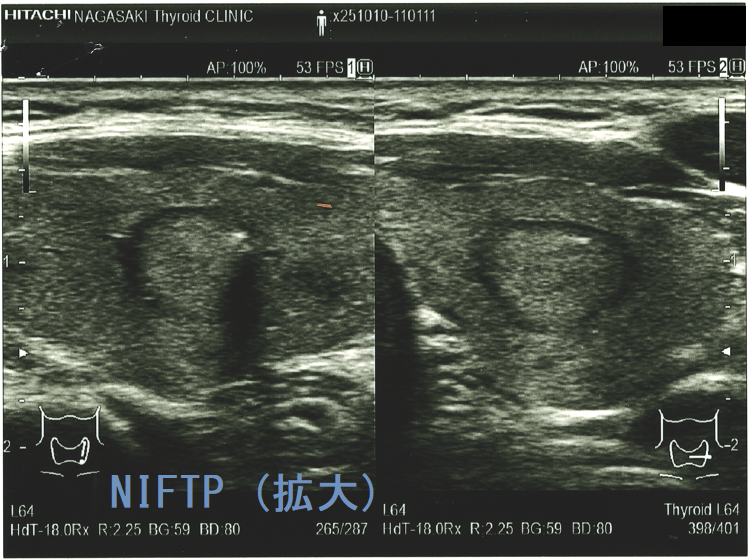

(a)Non-invasive follicular thyroid neoplasm with papillary-like nuclear features (NIFTP) 超音波(エコー)画像;見かけは濾胞型甲状腺乳頭癌、甲状腺濾胞癌、腺腫様結節と鑑別できまない

Non-invasive follicular thyroid neoplasm with papillary-like nuclear features (NIFTP)の超音波(エコー)所見は、

- 被膜が存在(被膜のない場合もある)

- 充実性、等エコーが多い

- 砂粒状石灰化を認めない

で、濾胞型甲状腺乳頭癌、濾胞性腫瘍(良性濾胞腺腫 、甲状腺濾胞癌)と超音波(エコー)所見にて鑑別できません。砂粒状石灰化のない濾胞型甲状腺乳頭癌なんて普通に存在します。NIFTPの60.1%は悪性を疑う所見が無いとされます[Endocrine. 2021 Jul;73(1):131-140.]。